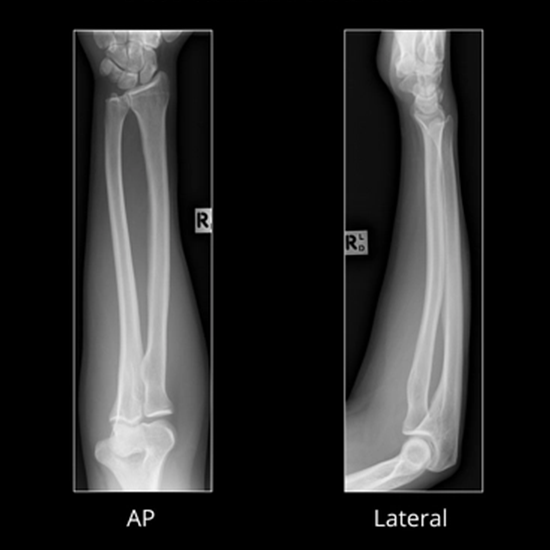

X-ray Both Forearm AP View

An X-ray of the forearm visualizes the bones of the forearm and the surrounding soft tissues (skin and muscles). The forearm consists of the elbow, the forearm bones (radius and ulna), and the wrist.